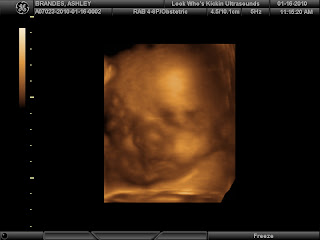

I never got to do the 4D ultrasounds with the other boys, so I knew that I wanted to try and get one done with this pregnancy (since it is my LAST one!). I booked my appointment at Look Who's Kickin' locally. We had such a great experience there! To start with, it was such a nice place! They took us right back and we started. Carson did not want to show us his face to start with. In the first picture you can see his right arm going over his face and his toes coming in at the middle of the frame. Poor little (HA!) guy, he's a pretzel in there!

Here was our first really good facial shot. The bubbly stuff over his mouth is the cord in the way.

Either he will have Daddy's nose, or he is smooshed in there. I'm gonna guess his is extremely smooshed.

Sweet baby gave us a smile!